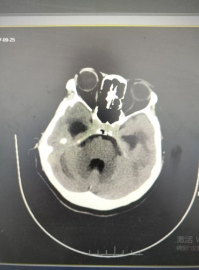

术前影像:CT提示明显交通性脑积水,脑室系统扩大。